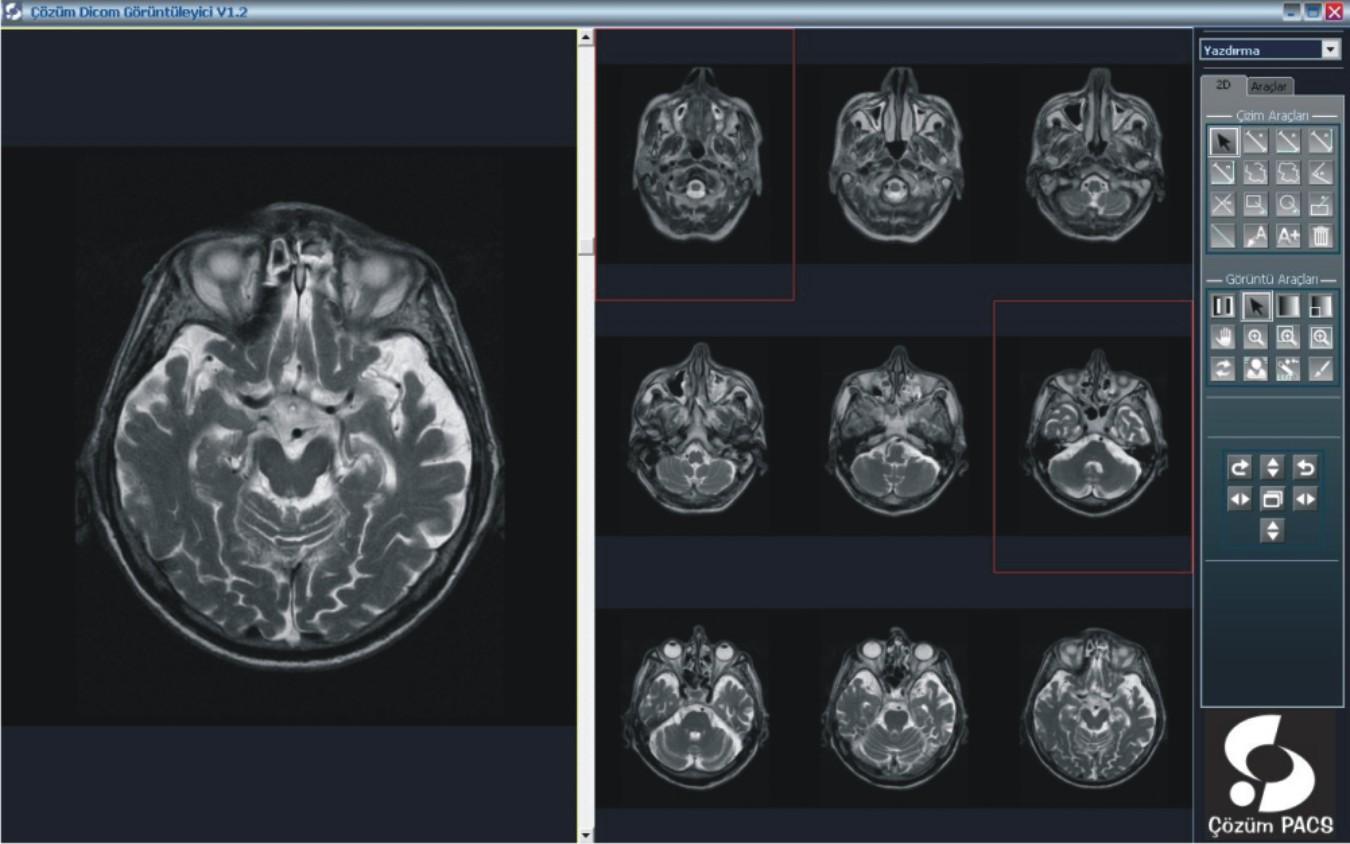

Hastanemizde bilgi yönetim sistemi olarak Çözüm HBYS'yi (Hastane Bilgi Yönetim Sistemi) kullanıyoruz. Güçlü bir entegrasyon sağlamak adına uluslararası standartlara haiz, tamamı Türk mühendislerine ait tek PACS olma özelliğindeki Çözüm PACS'ı tercih ettik.

PACS ile, dijital olarak elde edilen panoramik ve lokal radyolojik görüntüler (ultrasonografi, doppler, magnetik rezonans, tomografi v.b. cihazlardan elde edilen veriler) çevrimiçi ortamlarda dijital arşivleme yöntemleriyle saklanıyor. Kayıpsız bir şekilde, hızlı ve güven içinde saklanan bu görüntüler, gerektiğinde istemcide yeniden görüntülenerek kullanılabiliyor.

Merkezi veri tabanında bilgilerin depolanması ile oluşan dijital arşiv (görüntüler üzerinde işlem yapmaya izin verecek şekilde yüksek çözünürlükte saklandığı için ölçüm ve tanıya ilişkin işlemler kolaylıkla yapılabiliyor), bilgilerin yeniden kullanılmasını arşivlenen bilgilerin modern tanı yöntemleri ile incelenmesini sağlıyor. Dijital görüntüler üzerinde işlem ve ölçüm yapılabiliyor. Görüntüler ve raporların her an, her yerde (tüm iş istasyonları üzerinden sorgulama yapılarak) ulaşılabilir olmasına ve görüntü işleme ve ölçüm (mesafe, açı, uzunluk, yoğunluk) yapılabilmesine imkan sağlıyor.

PACS, tanı ve teşhislerde daha doğru sonuçlar elde edilmesini sağlayarak  sonuçları  yorumlama ve raporlama süresini hızlandırıyor. Görüntülerin karşılaştırılması ve radyolojik bulguların geriye dönük değerlendirilmesi, karşılaştırmalı raporların incelenmesi, hekimin hastalığın gelişim sürecini daha iyi kavramasını ve doğru teşhisi daha hızlı bir şekilde koyabilmesini sağlıyor. Yedeklenen PACS görüntüleri istenildiğinde hastalara CD-DVD halinde veriliyor.